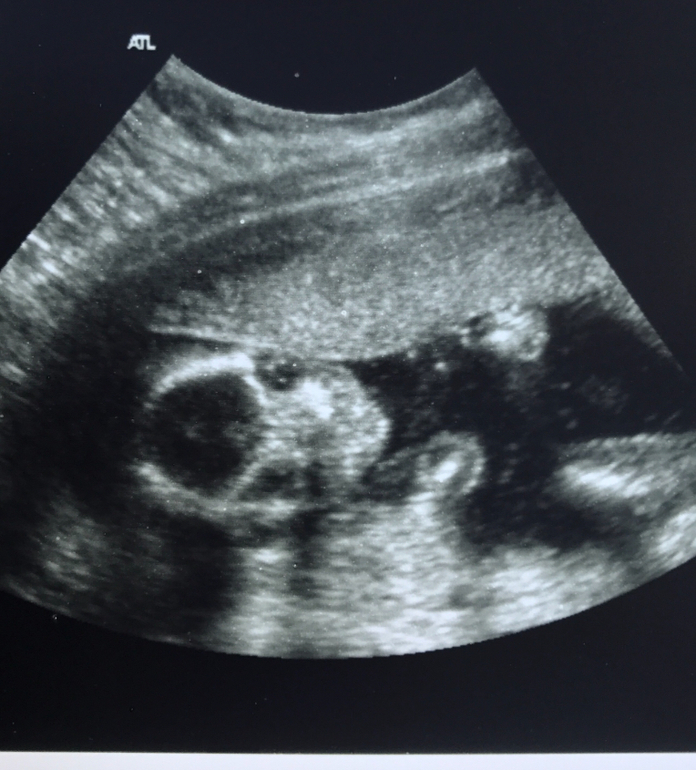

УЗИ 18 недель.

УЗИ, КТГ, доплерСегодня без одного дня 18) С первым сыном я ходила на УЗИ точно так же, в 17,6

Ходила узнать пол и сравнить параметры детишек. Удивительно то, что с сыном я забеременела ровно на месяц раньше, 6 лет назад . И была на УЗИ тогда 14 марта. Сегодня 14 апреля) Такое совпадение случайно)) Ну и я смогла наконец таки узнать кто же живет внутри. Скажу сразу, что пол рассмотрели только вагинально, так как крошка сидела на попе и сжимала ножки сначала. Но потом стало ясно кто же это чудо. И таки да, так как я чувствовала, так как мечтал мой сынок, это ОНА, наша девочка.

Фото пола) и сравнение параметров мальчика и девочки на одном сроке, под кат:

Первый сын/ Дочка

Плацента по задней стенке/по передней

Толщина плаценты 20 мм/ 25мм

Длина шейки матки 39 мм/ 35мм

Сердце - 140 ударов в минуту/136.

БПР - 39 мм/ 38мм

ОГ - 143 мм/136мм

ОЖ - 123 мм/ 130мм

СДГК - 35 мм/ 40мм

ДС - 28 мм/ 26мм